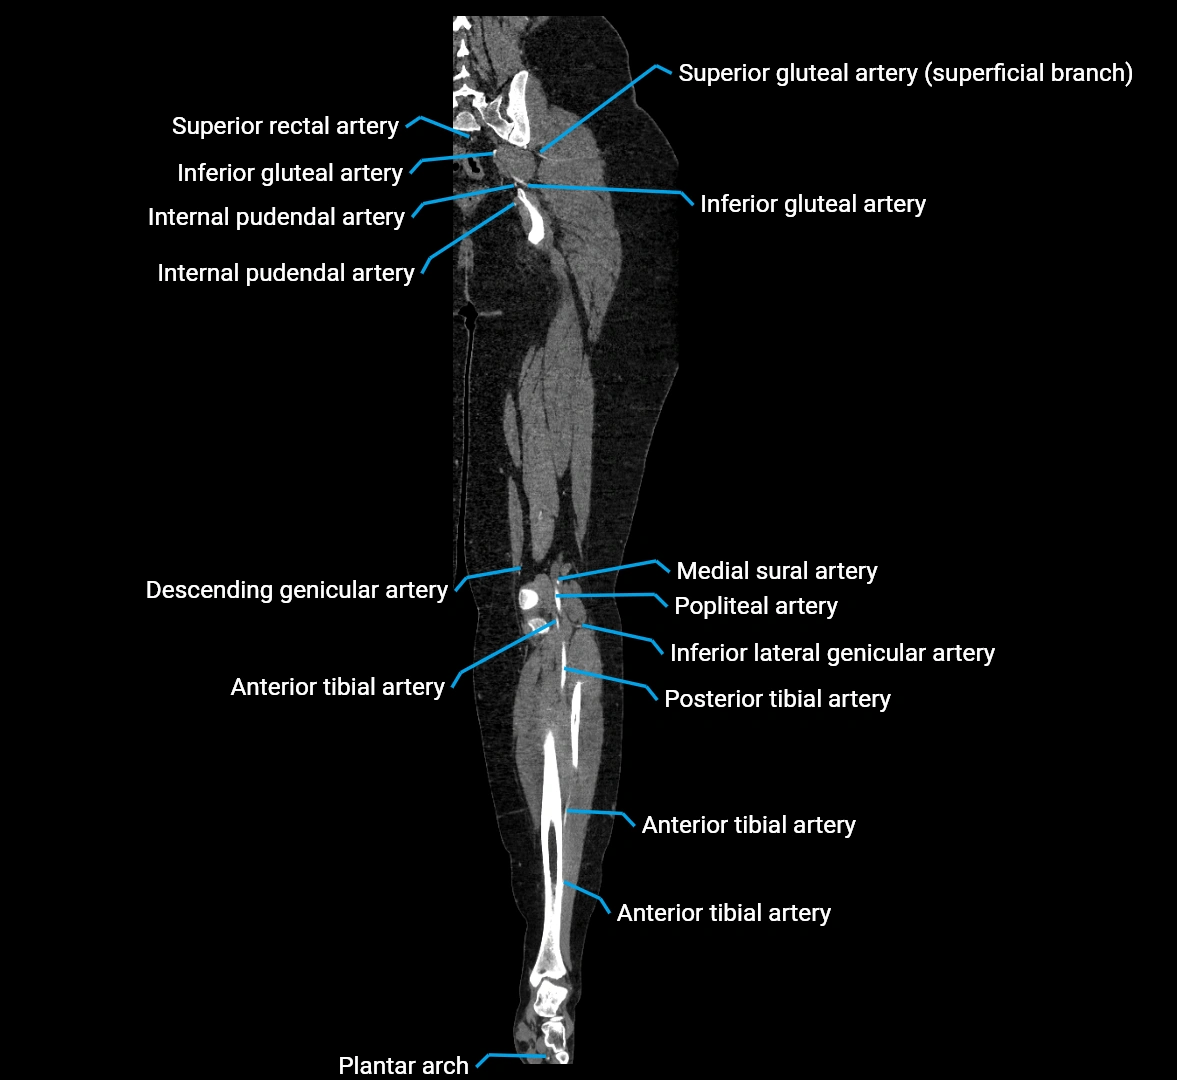

Contrast-enhanced CT (CTA):

• Gold standard for abdominal aortic imaging

• Provides excellent detail of lumen, wall, aneurysm, thrombus, and branch vessels

• Multiplanar and 3D reconstructions help in aneurysm measurement, stent graft planning, and dissection evaluation